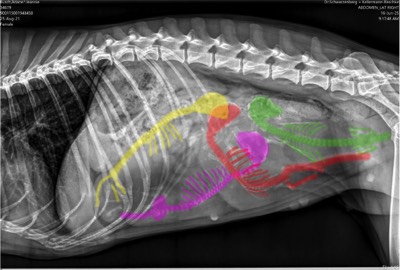

Unsere bezaubernde Jeannie „Tova‘s Riesling Surprise in Germany“ wurde Ende April von unserem charmanten Mio „Golden Nugget's Achilles“ gedeckt.